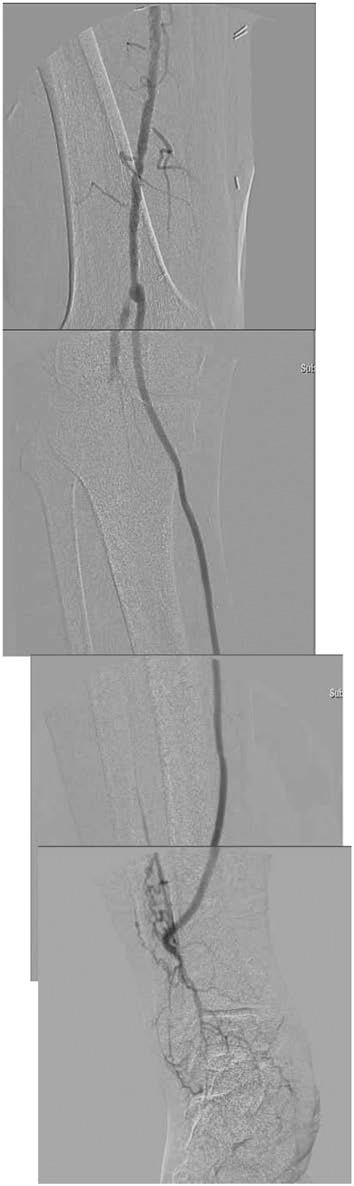

与糖尿病相关的最重要的血管病变是动脉硬化闭塞症(ASO)。与产生神经源性溃疡的糖尿病足病变进行鉴别诊断非常重要,必须尽快诊断是否存在缺血。据报道,糖尿病会使 ASO 变得更加严重,往往会导致下肢截肢。除了需要早期适当控制糖尿病外,血管外科医生还需要对溃疡和坏死病例立即进行血管重建,并积极采用长期预后良好的手术治疗。(本文译自《Jpn J Vasc Surg 2023; 32: 105-109》)。

The most important vascular lesion associated with diabetes is arteriosclerosis obliterans (ASO). Differential diagnosis from diabetic foot lesions that produce neurogenic ulcers is important, and the presence of ischemia must be diagnosed as soon as possible. It has been reported that diabetes makes ASO more severe and often leads to lower extremity amputation. In addition to the need for appropriate early control of diabetes, vascular surgeons are required to perform immediate revascularization in cases of ulcer and necrosis, and to aggressively use surgical treatment with good long-term prognosis. (This is a translation of Jpn J Vasc Surg 2023; 32: 105-109.).